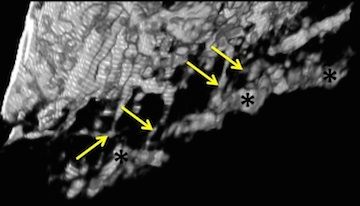

• Lamina cribrosa vessel and collagen beam networks are distinct

• S Waxman ,BL Brazile, B Yang, PY Lee, Y Hua, AL Gogola, P Lam, AP Voorhees, III JF Rizzo, TC Jakobs, IA Sigal

• Experimental eye research, 215, 108916, December 2021.

image

• S Waxman, BL Brazile, B Yang, PY Lee, Y Hua, AL Gogola, P Lam, AP Voorhees, III JF Rizzo, TC Jakobs, IA Sigal